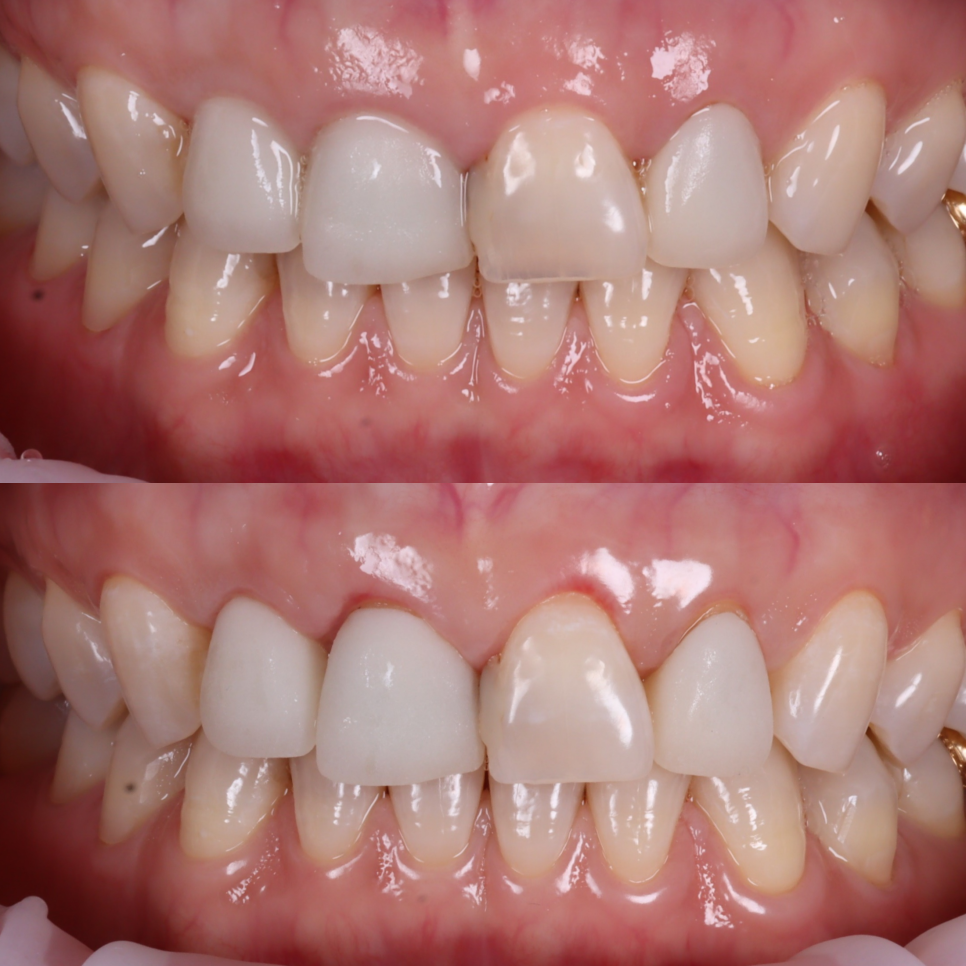

잇몸이 안정된 뒤 기존 보철물은 전부 제거하고 치아 상태를 다시 확인했어요.

치아 삭제가 최소로 가능한 부위는 라미네이트로

돌출과 구조적인 한계가 있는 치아는 크라운으로

중간에 임시치아를 사용하면서 웃을 때 느낌, 발음, 입술 닿는 느낌까지 하나씩 확인해가며 조정했죠^^

최종 보철을 완성한 뒤, 환자분께서 요청하신 잇몸 라인과 균일한 치아 색상, 자연스러운 치아 형태가 잘 구현되었는지 확인했습니다.

또, 혀에 걸리는 느낌이나 불편한 부위는 없는지, 전체적인 교합 상태까지 면밀히 점검하며 세밀한 조정을 거쳐 치료를 마무리했습니다.